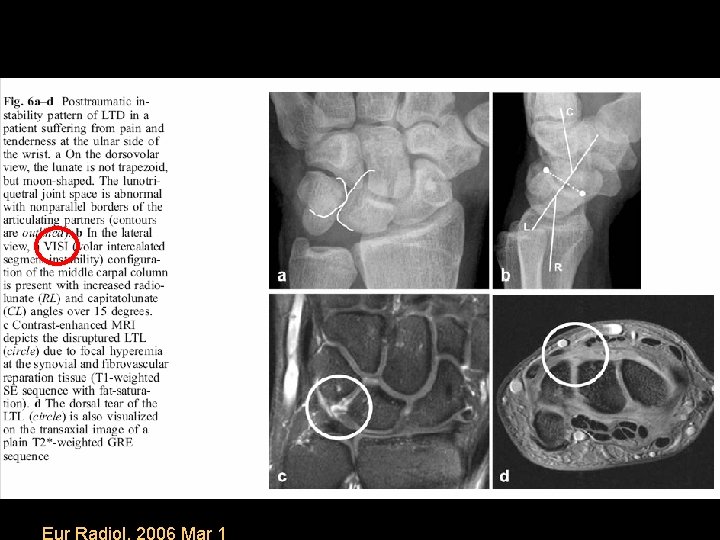

Static Midcarpal Instability • Static MCI results in flexion of the proximal carpal row and VISI

Eur Radiol. 2006 Mar